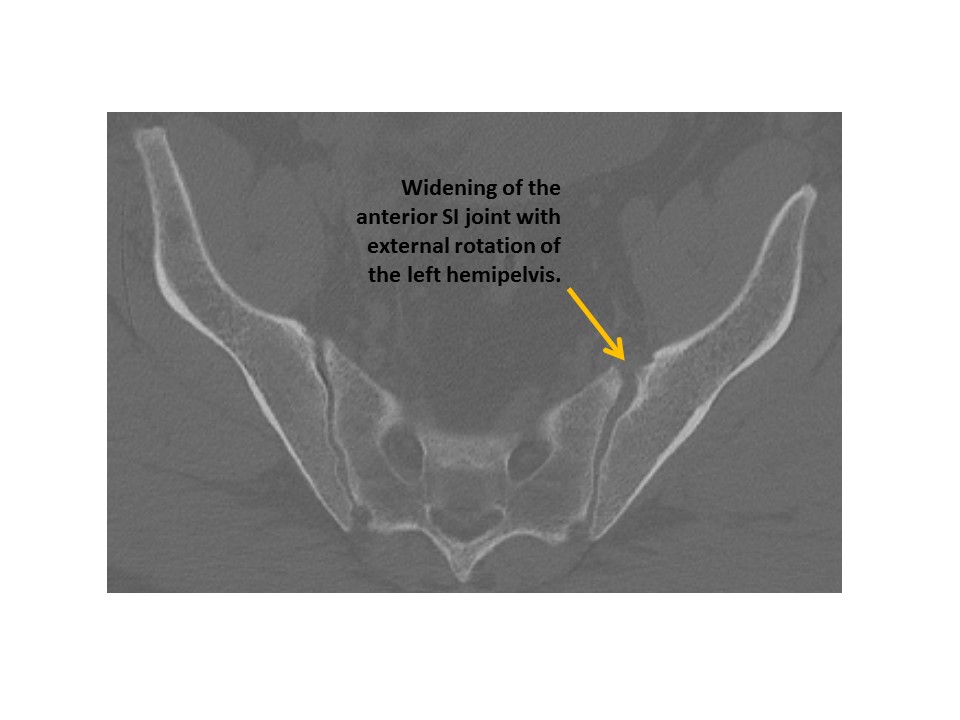

SACRUM and SACROILIAC JOINTS

The sacroiliac joints are widened and asymmetric. [Yes/No]

There is vertical subluxation of the sacroiliac joints. [Yes/No]